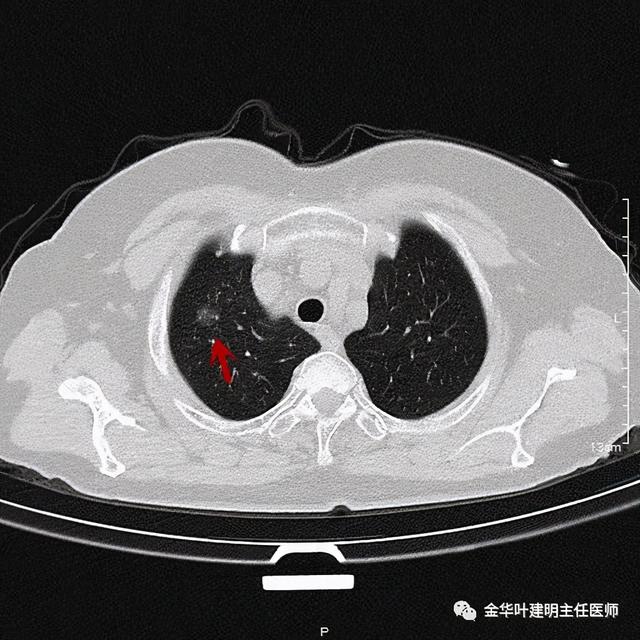

患者为女性 , 今年76岁 , 平时体质甚好 , 家务及地里劳动都胜任 , 头发仍乌黑(我自己倒有一半白发了) 。 肺功能与血气分析正常 。 CT检查图像如下:

可见右肺上叶混合磨玻璃结节 , 有明显分叶征 , 瘤肺边界虽然欠清楚 , 但轮廓比较清晰 。 看着也许会考虑炎性 , 但总觉得其比较僵硬 , 看去不舒服 。 这种病灶一是如果持续存在就极可能是肺癌 , 二是靶扫描显示更清晰的细节 , 如果瘤肺边界还是清楚的 , 也基本是肺癌 。 我们回顾发现其于2019年3月在我们医院做过CT平扫 , 当时报告如下: